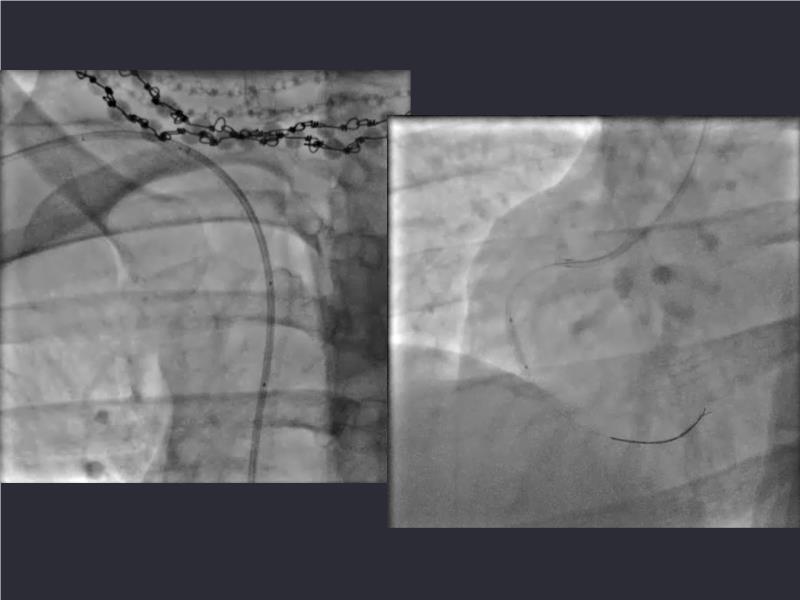

This session is a valuable resource for grasping innovative strategies in handling bifurcation and extended diffuse lesions through dedicated stenting solutions. Explore insights into the advanced Myval next-generation THV technology, unveiling its distinctive features, procedural advantages, and clinical outcomes across a diverse patient pool. Gain understanding into the CorAlign technique, ensuring accurate commissural and coronary alignment while maintaining coronary access. Additionally, delve into the techniques for precise sizing, positioning, and deploying of Myval THV.

- To understand the CorAlign technique which enables predictable and precise commissural and coronary alignment thus preserving coronary access